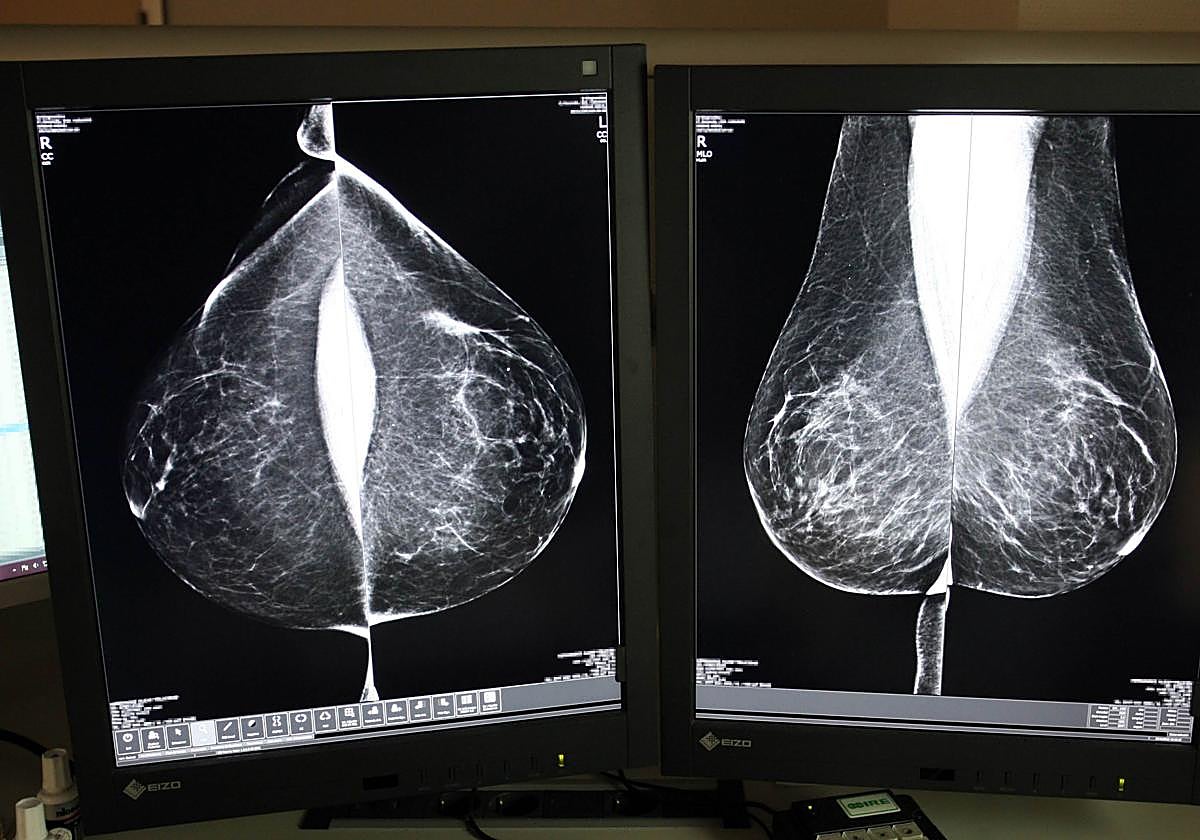

Mamografía. Rubén Cacho

Externalizan las mamografías para poder llegar a 122.000 mujeres en Castilla y León

Sacyl ha subcontratado durante un año por 1,8 millones de euros la doble lectura para agilizar los tiempos del cribado

La Consejería de Sanidad vuelve a externalizar el servicio de doble lectura e informe de mamografías este año para dar respuesta a la alta cobertura del Programa de Detección Precoz de Cáncer de Mama.

El programa de cribado está dirigido actualmente a mujeres con edades comprendidas entre los 45 y 74 años, franja de edad que se amplió al grupo de 69 a 74 a finales de 2023. La inclusión de este nuevo grupo ha elevado el volumen de pruebas a más de 122.000 mamografías anuales.

Desde su puesta en marcha en 1992, el programa se basa en el sistema de doble lectura, un protocolo que establece que cada mamografía sea evaluada por al menos dos radiólogos, de forma independiente, aumentando así la fiabilidad de los diagnósticos. Sin embargo, aumenta la carga de trabajo y plazos, motivo por el cual Sacyl ha optado, de nuevo, por externalizar el servicio al que el año pasado dedicó casi cuatro millones.

En 2023, último dato disponible, se realizaron un total de 122.193 mamografías, de las que 7.503 (un 6,14%) tuvieron resultado sospechoso positivo y fueron derivadas a Atención Hospitalaria para realizar el diagnóstico final. Por provincias, el porcentaje de pacientes derivadas osciló entre el 3,7% de Zamora y el 9,9% de Soria.